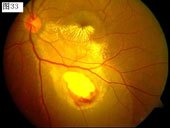

33 34 35 36